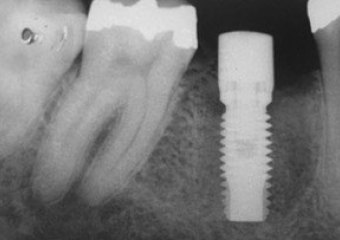

Raio X após a instalação do implante